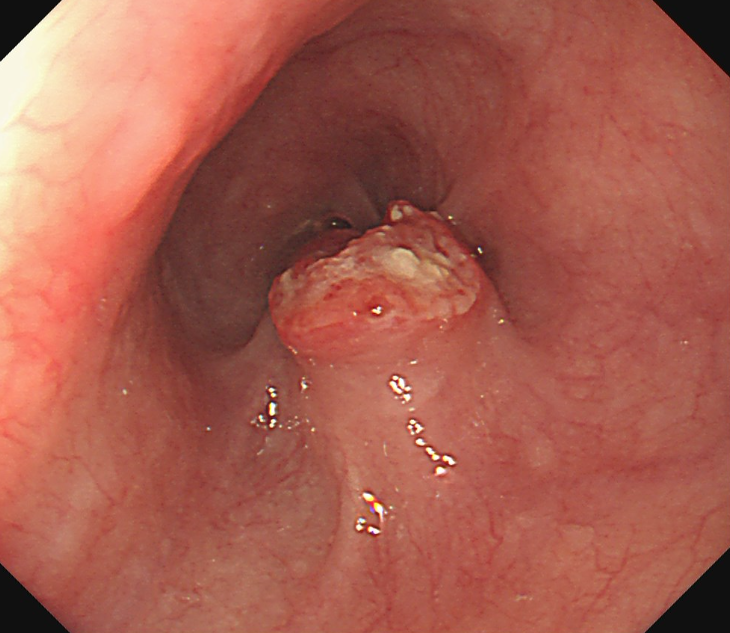

食道がんの検査は、がんかどうかを確定するための検査と確定された後に行う進行度を判断するための検査があります。まず確定するための検査としては、内視鏡(胃カメラ)で直接病変を観察する内視鏡検査が行われます。内視鏡で異常がみられる場合は組織を採取し、顕微鏡で観察する生検を行い診断が確定されます。

内視鏡(胃カメラ)画像